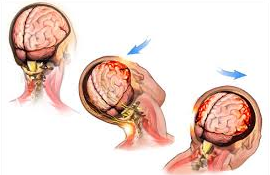

In very rare cases, a blood clot can form on a brain after a person suffers a concussion. This is the primary reason it is so very important to get help as soon as possible. Better for a doctor to tell you there is nothing to worry about then to be unsure.